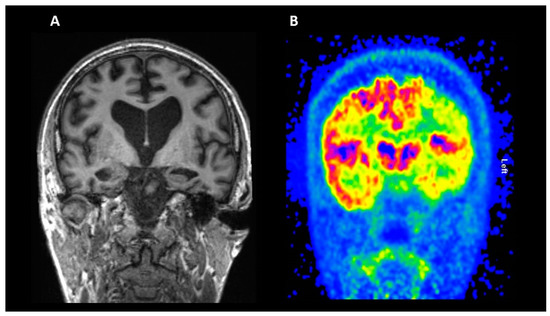

2.1. Structural Magnetic Resonance Imaging (MRI)

2.2. Fluorodeoxyglucose (FDG) PET

| Glucose Metabolism | 18F-FDG | Reduced uptake in posterior cingulate, hippocampi, and medial temporal structures is typical in AD and MCI, with a subsequent spreading to the whole cortex as the disease progresses. The reduction in glucose metabolism in regions like precuneus and posterior cingulate has been demonstrated to be associated with the severity of the cognitive impairment | [121,126] |